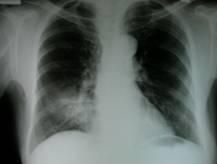

末梢血白細胞總數可升高。胸部X線檢查可見肺紋理增多,心臟轉位;支氣管造影可顯示支氣管擴張,多見於兩肺下葉。

對支氣管擴張伴內臟轉位的患者要考慮Kartagener的可能性。影像學檢查是臨床診斷Kartagener綜合徵的重要依據。胸部X線片、CT掃描、超聲檢查均可發現內臟轉位。